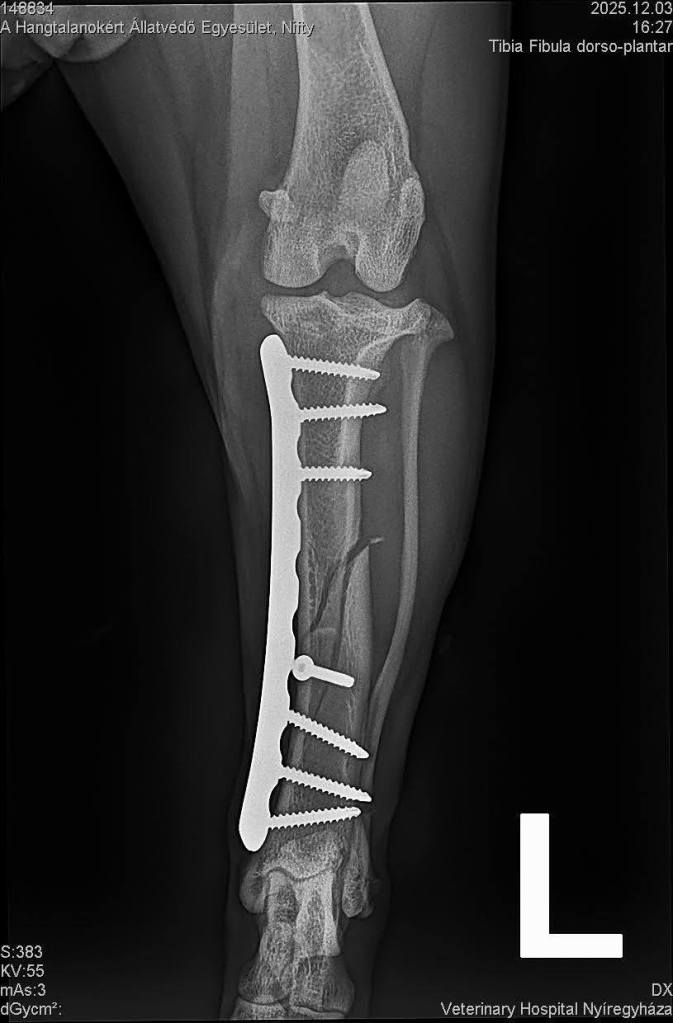

Den Röntgenbildern ist zu entnehmen, dass mehrere Brüdhe (Schienbein, Oberschenkelknochen, angebrochenes Becken) behoben wurden. Stunden vergingen, doch die tapfere Mausi hat sich gut geschlagen. ![]()

Jetzt darf sie sich im Inneren des Tierheims ausruhen und bekommt die Hilfe, die ihr zusteht. Zum Glück wurde kein Nerv beschädigt, Nifty kann sich eigenständig entleeren und ihre Wirbel wurden wieder eingerenkt.